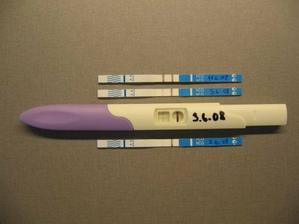

4.6. 08» Zatím jsem si dělala jen testy, na první vyšetření jdu ve čtvrtek 12.6.